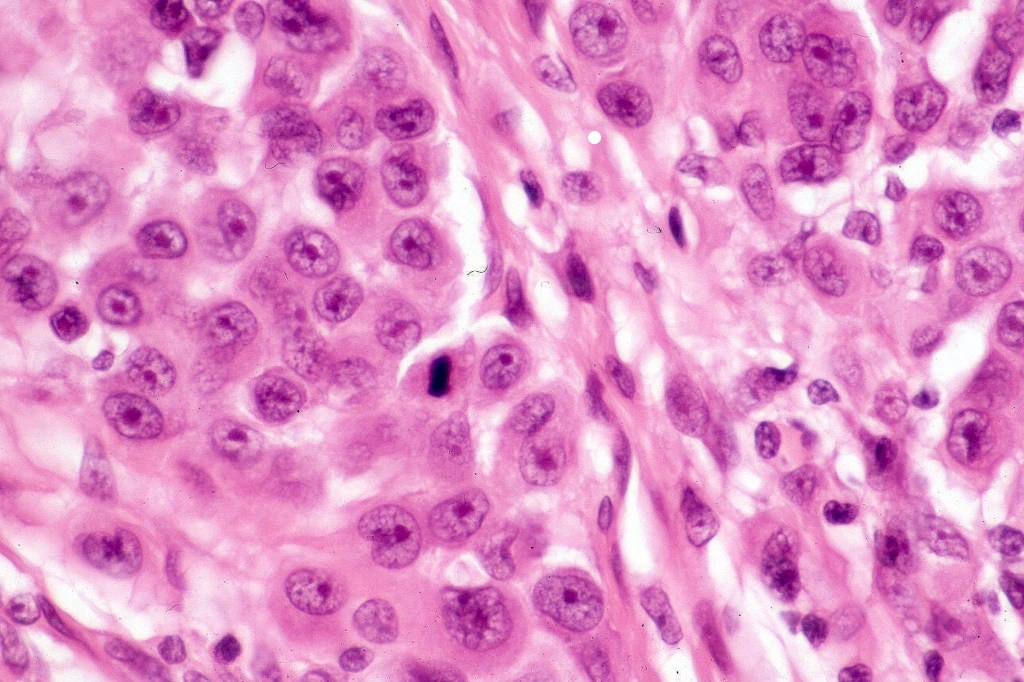

Melanoma arising in a congenital nevus

•Although the vast majority arise in giant forms, they may be encountered in smaller lesions & can be present at birth

•Develop in the dermal component

•Typical melanoma, nevoid melanoma, small cell melanoma, pleomorphic/anaplastic melanoma, melanoma with heterologous differentiation & malignant nerve sheath-like melanoma.

This melanoma arose in a small congenital nevus of the scalp. It metastasized widely. Varying features in different fields.